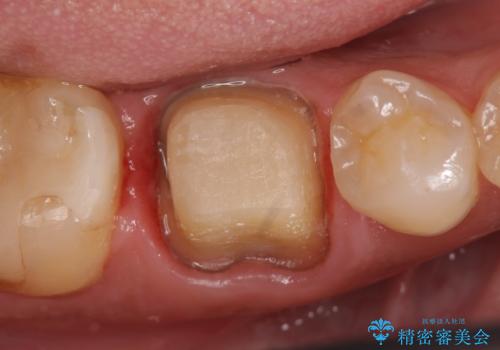

- ものを咬むと右下の奥歯が疼くといらっしゃった方の症例です。

検査の結果X線上で右下6に根尖病変を認めたため、再根管治療を行いました。

症状が治まったのを確認後、オールセラミッククラウンによる補綴を行いました。